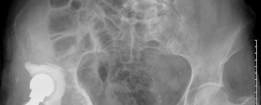

History of presenting complaint : Presents with a draining wound and well-fixed cementless components with a constrained liner due to absent abductor mechanism (Fig. 19.12). Treated with Prostalac and six weeks of IV antibiotics (Fig. 19.13). At the 6-week point, the patient sustained a ground level fall with an acetabular fracture and displacement of the acetabular Prostalac (Fig. 19.14).